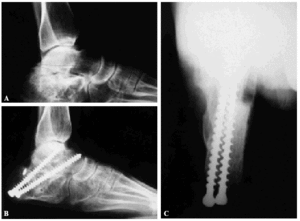

Una vez extraído y con ayuda de un separador se introdujo el injerto en la parte posterior de la articulación previamente decorticada, y controlando la alineación para no producir un varo de talón, se fijó con dos tornillos de 6,5 mm de rosca total no canulados, desde el talón introduciéndolos de plantar lateral a medial superior, uno hacia el cuerpo del astrágalo cogiendo el bloque de injerto y otro hacia el cuello del mismo hueso más medial. Se realizaron radiografías intraoperatorias en 4 proyecciones para comprobar la correcta alineación del astrágalo con respecto al tobillo y pie y la situación de los tornillos (fig. 1). Cuando existía una desviación en varo del talón se realizó una artrodesis subastragalina in situ y previamente a la fijación con tornillos una osteotomía de Dwyer o bien de lateralización de la tuberosidad posterior (fig. 2).

Figura 1. Paciente que sufrió una fractura de calcáneo por accidente de tráfico hace 9 años, siendo tratada ortopédicamente. A: la radiografía lateral muestra un hundimiento de la articulación subastragalina posterior con disminución del ángulo de Böhler. B: la radiografía postoperatoria muestra cómo se ha reducido el calcáneo debajo del astrágalo, recuperando la altura perdida mediante la colocación de un injerto estructurado de cresta ilíaca, mejorando además la alineación del astrágalo con el tobillo. C: imagen axial que muestra cómo existe un buen alineamiento de la tuberosidad posterior del calcáneo y cómo éste está bien reducido por debajo del astrágalo.